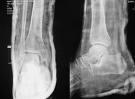

檢查

影像學檢查,踝關節脫位診斷並不困難,常規X線攝片很容易證實上述診斷;特殊檢查CT,掃描容易檢出合併存在的微小骨折。治療